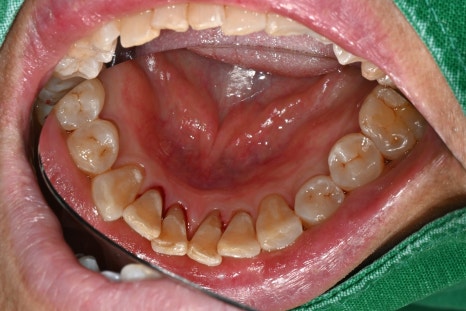

▼ 아래는 본원에서 치료한 실제 스케일링 전후 사진입니다.

-치료 전

오른쪽 사진: 전체적으로 잇몸이 부어있습니다. 특히 아래 앞니쪽에 치석이 다량으로 쌓여있어 잇몸 염증을 유발하는 상태입니다.

- 치료 후

오른쪽 사진: 치석이 제일 많았던 아래 앞니 사진 입니다. 치석 제거후 깨끗해진 상태입니다.